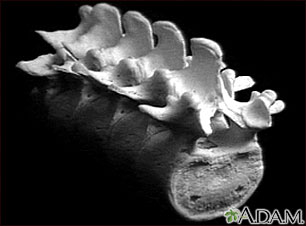

Vertebra, lumbar (low back)

Vertebra, lumbar (low back)

These are the five vertebra of the lower back. The last vertebra (on the upper left of the picture) attaches to the sacrum, and the top vertebra (on the right of the picture) attaches to the thoracic section of the back. The vertebra are broader and stronger than the other bones in the spine. This allows them to absorb the added pressure applied to the lower back, but this area remains a common site of injury. The vertebra are numbered from one to five and are labeled L1, L2, L3 etc. from the higher bones to the lower.